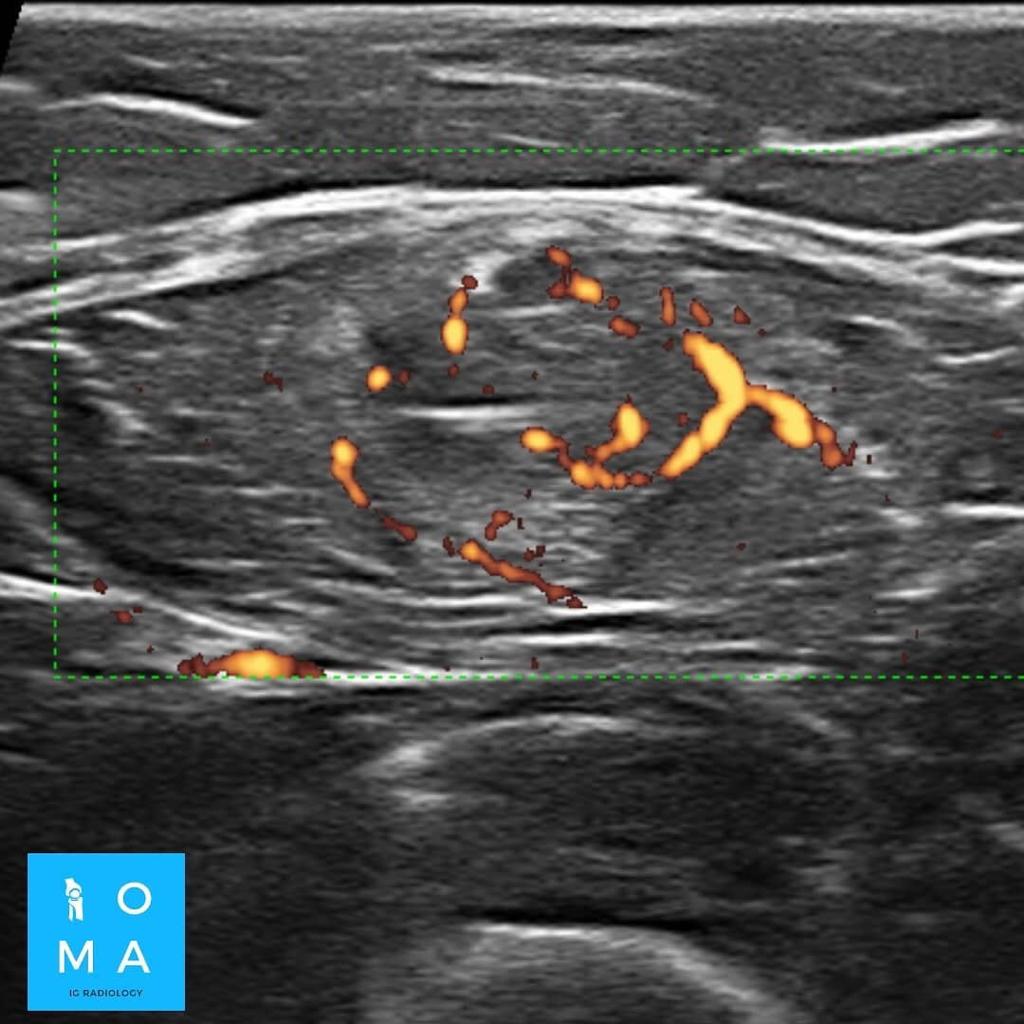

🔹En un segundo tiempo se realiza ecografía dirigida, confirmando los hallazgos a nivel del tendón central del músculo recto

anterior del cuádriceps derecho, presentando desgarro grado II, asociado a un

aumento del flujo vascular al examen Power doppler.